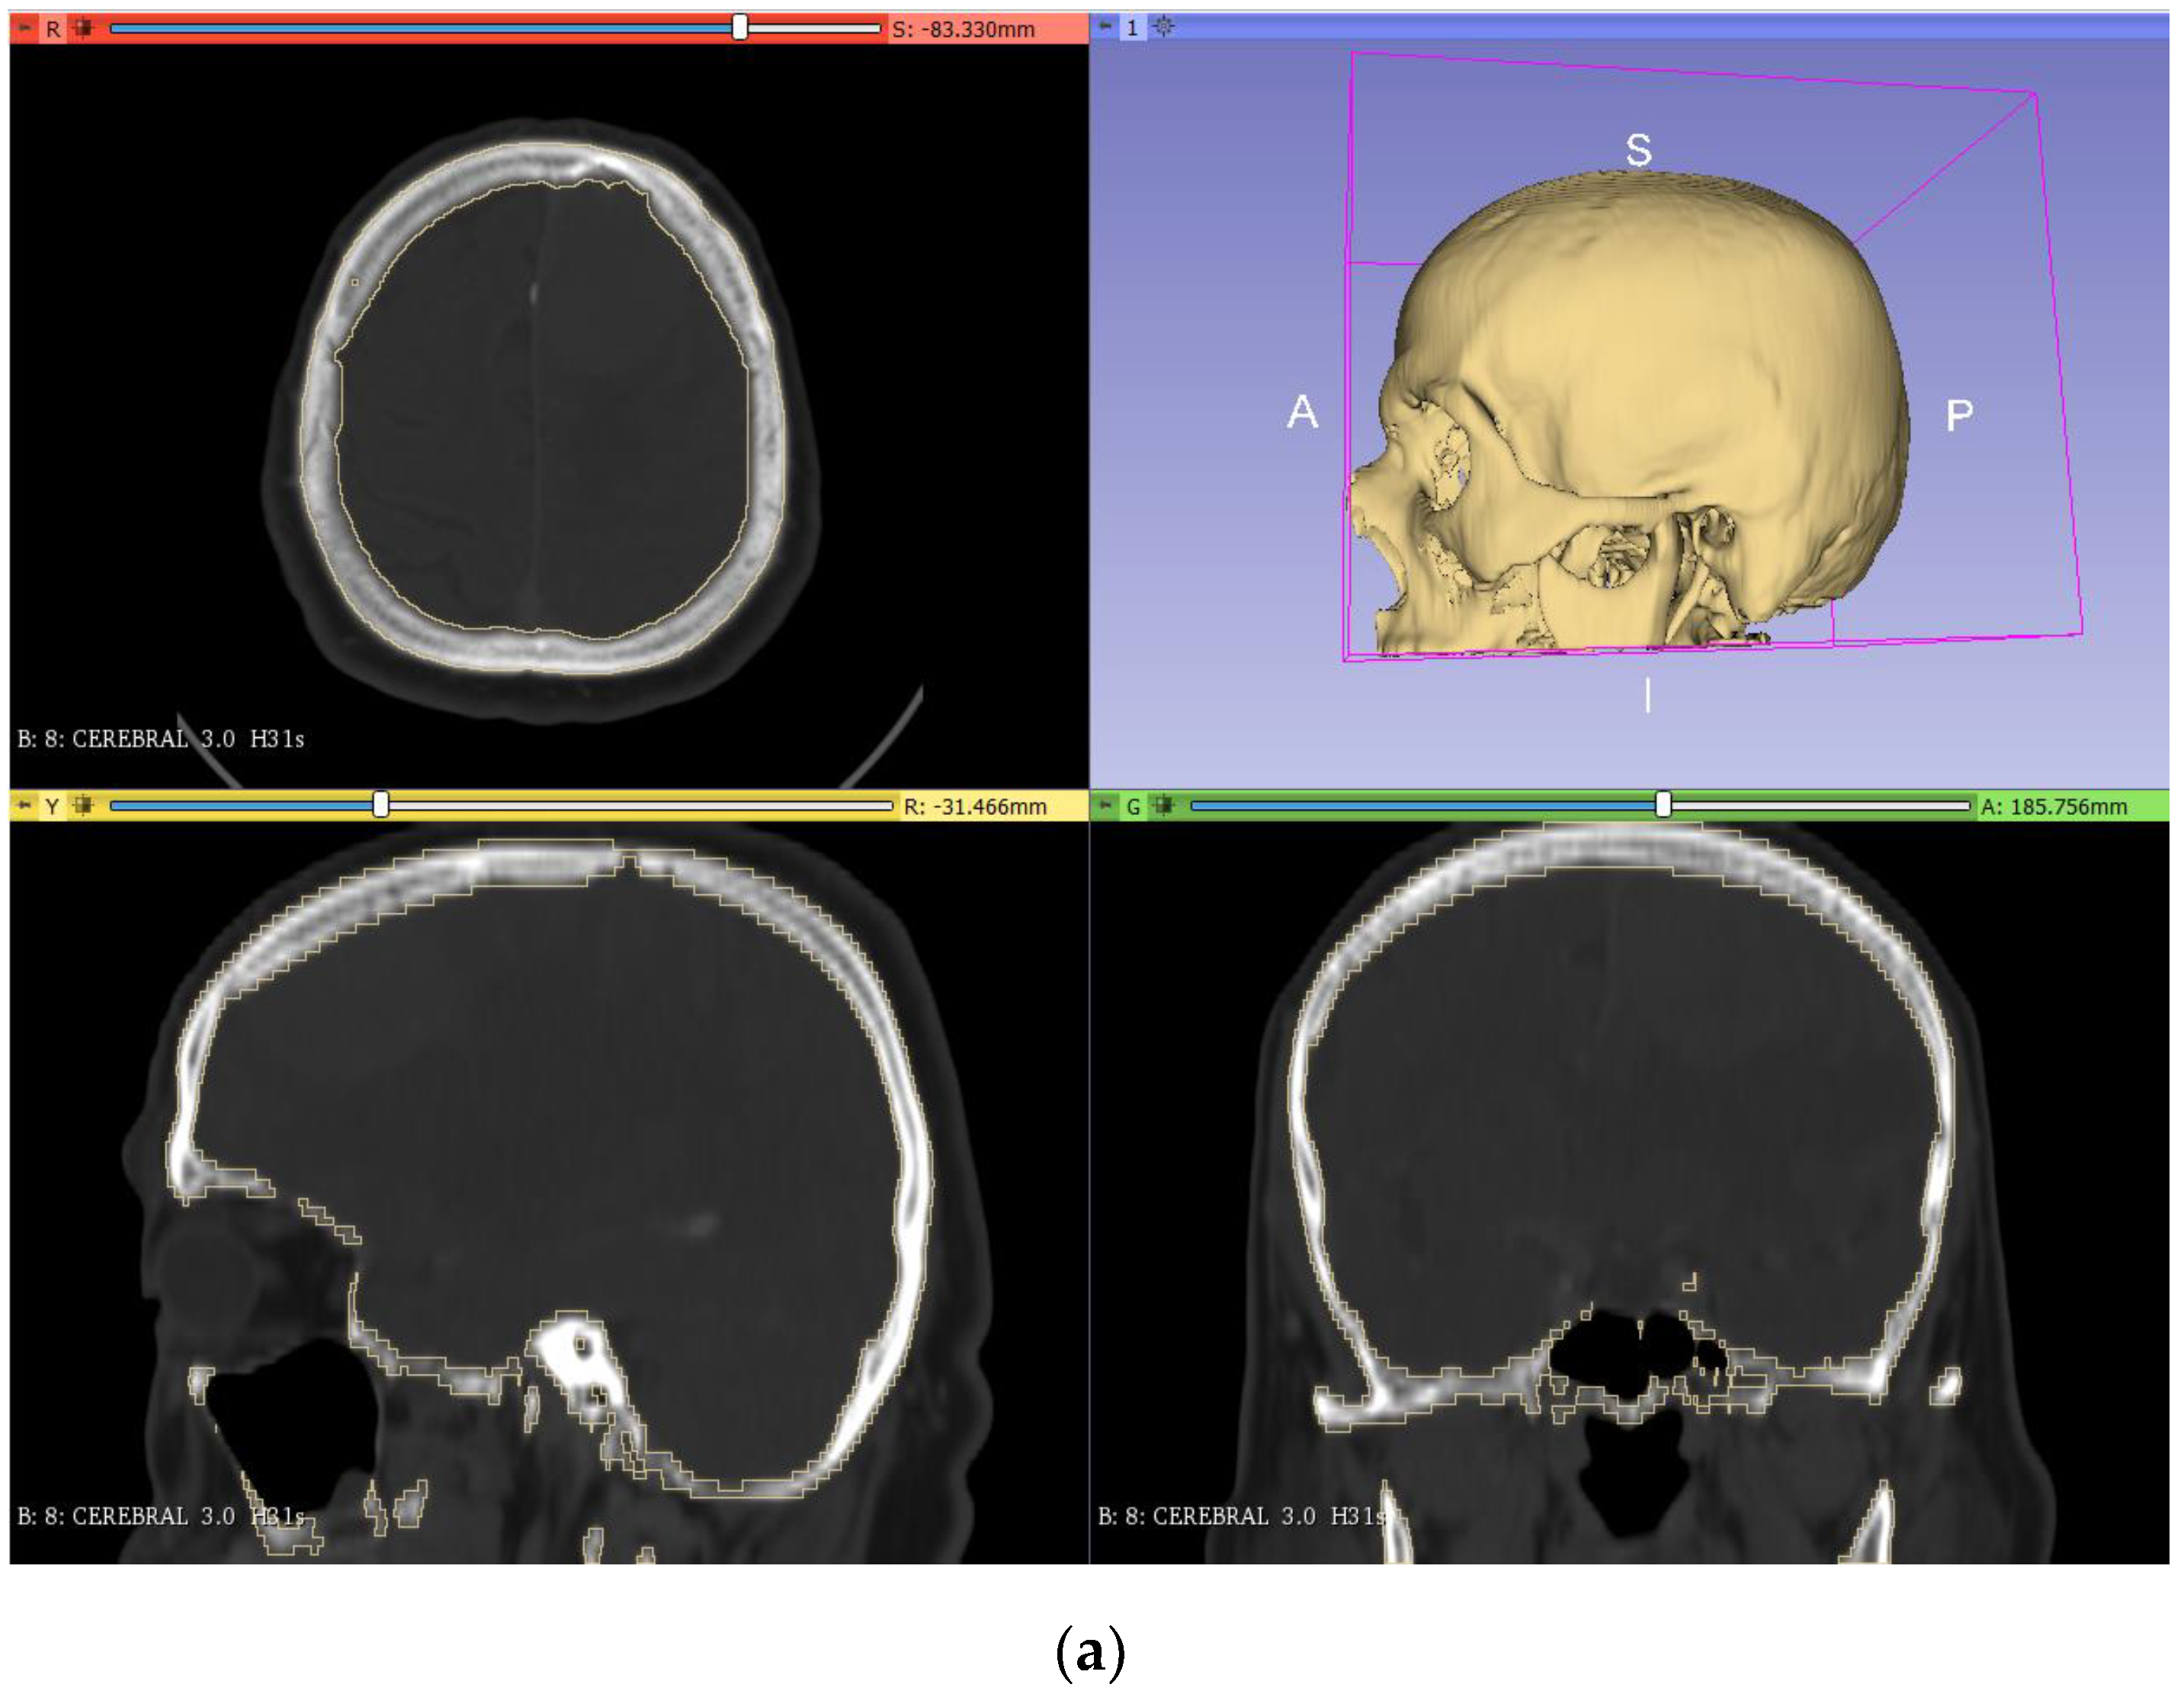

To obtain the final model of the skull, we performed the segmentation (Figure 2a) and cutting (Figure 2b) with the different 3DSlicer tools. For the segmentation step, the ‘threshold’ tool (in the segment editor) was used, adjusting the range values until the selected pixels matched the zone of the bone. After this, the cutting of the lower part of the bone was carried out by using the ‘scissors’ tool. Finally, the resulting model was saved as an STL file and converted into a solid STL file in the Meshmixer software (‘make solid’ tool, in the ‘edit’ menu).

Figure 2.

Segmentation (a) and cutting (b) of the skull model from the DICOM images in 3DSlicer.